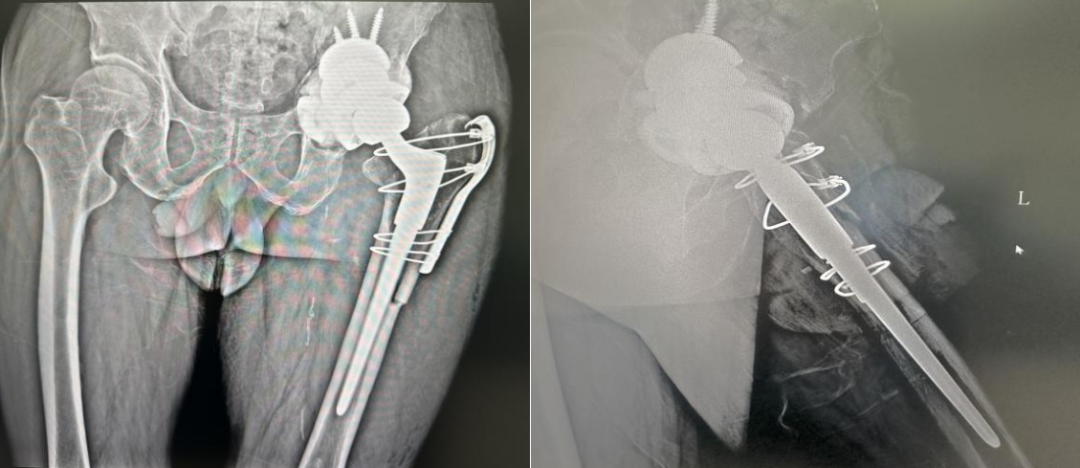

面对这一难题,林源主任医师团队决定采用国际较为领先的“杯中杯”技术。该技术通过精准利用残留宿主骨,压配植入多孔钽金属杯,重建髋臼巨大骨缺损;随后在钽杯基础上安放定制骨水泥臼杯,精准恢复髋关节旋转中心及生物力学偏心距。术中,林源主任医师团队依据术前3D影像建模数据,精确计算钽杯直径与位置,最终实现假体稳定支撑与关节功能重建。

术后正位(左)术后侧位(右)

林源主任医师表示“杯中杯”技术不仅解决了复杂骨缺损的力学重建难题,其多孔钽材质更能促进骨长入,为远期稳定性提供保障。病区护士长季长高表示,骨病中心四部关节与运动医学科理推行“加速康复外科(ERAS)”理念,从术前教育到居家康复形成闭环管理,让患者真正实现“早活动、少痛苦、快回归”。